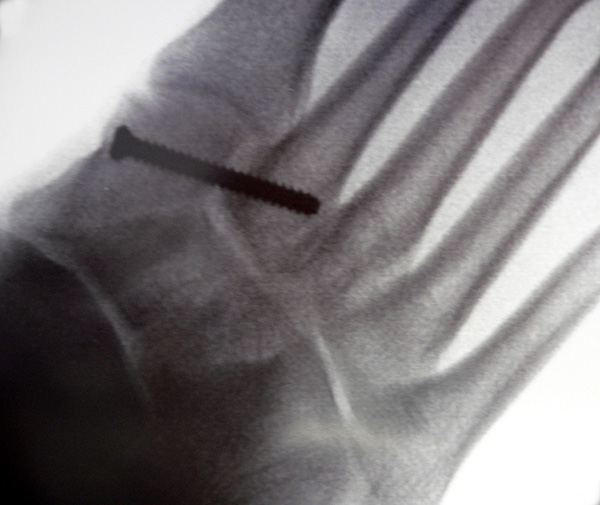

Bei frischen Verletzungen gelingt meist die geschlossene Reposition durch eine Repositionszange unter Bildverstärkerkontrolle. Anschließend wird über eine kleine mediale Inzision ein Kirschnerdraht vom Os cuneiforme mediale in die Metatarsale II-Basis gebohrt und das Lisfranc-Ligament durch eine Stellschraube in anatomischer Stellung ruhiggestellt. Durch weitere Schrauben lässt sich bei Bedarf das Tarsometatarsale I-Gelenk und der Raum zwischen Os cuneiforme I und II stabilisieren. Nach Lagekontrolle unter dem Bildverstärker wird eine durchbohrte Schraube mit durchgehendem Gewinde eingebracht (Abb. 14). Von der Verwendung von Zugschrauben wird abgeraten, da diese eine unnötige und unphysiologische Kompression der Gelenkflächen erzeugen.

Zum Lesen der Bildbeschreibung und zur Vollansicht bitte das Bild anklicken.

Verwendet werden kanülierte oder Standard-Kleinfragmentschrauben. Die Verwendung von 2,0 mm Kirschnerdrähten ist ebenfalls möglich. Hier besteht allerdings ein erhebliches Risiko der Lockerung und Dislokation 15. Thordarson und Hurvitz (2002) 16 berichten über den Einsatz von resorbierbaren Schrauben. Gelingt die geschlossene Reposition nicht, was insbesondere bei verzögerter Diagnostik der Verletzung aufgrund der ausgeprägten Narbenbildung zwischen dem I. und II. Strahl der Fall sein kann, so wird über einen dorsalen Zugang das Narbengewebe ausgeräumt und anschließend nach Reposition die durchbohrte Schraube gesetzt. Postoperativ schließt sich eine achtwöchige Phase mit vollständiger Entlastung an. Der Patient ist darauf hinzuweisen, dass eine höhere Belastung des Fußes ein hohes Risiko des Schraubenbruches beinhaltet und dass eine gebrochene Schraube schwierig zu entfernen ist. Eine Teilbelastung mit 20 kg wird in Verbindung mit einer nach Fußabdruck angefertigten Einlage nach der achten Woche erlaubt. Die Metallentfernung erfolgt 12 Wochen postoperativ. Anschließend wird die Belastung auf das volle Körpergewicht gesteigert. Der Trainingsaufbau erfolgt stufenweise. Radfahren und Schwimmen ist rasch nach der Metallentfernung möglich; mit einem Lauftraining kann 4 Wochen nach der Metallentfernung begonnen werden. Bis zur Rückkehr in den Wettkampfsport vergehen erfahrungsgemäß 6 Monate. Das Tragen einer abstützenden Einlage wird für mindestens 1 Jahr empfohlen, wobei nach 6 Monaten von der statischen Abstützung zu sensomotorischen Einlagenkonzepten gewechselt werden kann (Abb. 15).